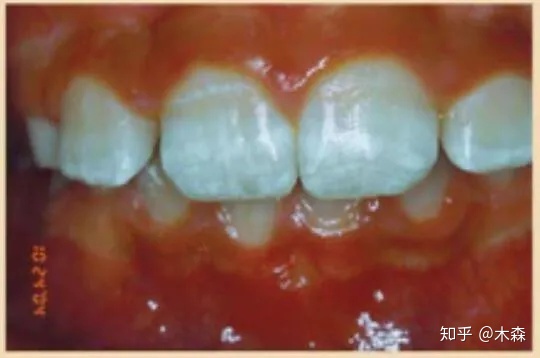

图:牙釉质2级缺陷,表面粗糙,且存在轻微的水平凹槽 - Source:http://rdhmag.com/patient-care/pediatrics/article/16404254/clinical-suspicion-of-celiac-disease

第2级,牙釉质存在轻微的结构缺陷。牙齿表面粗糙,且带有水平的凹槽和麻点,牙釉质的颜色和透明度都存在改变。